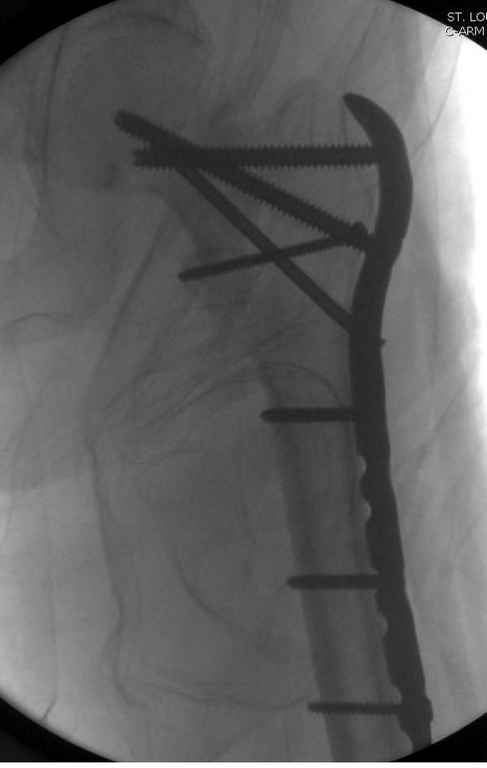

Здесь пара похожих случаев.